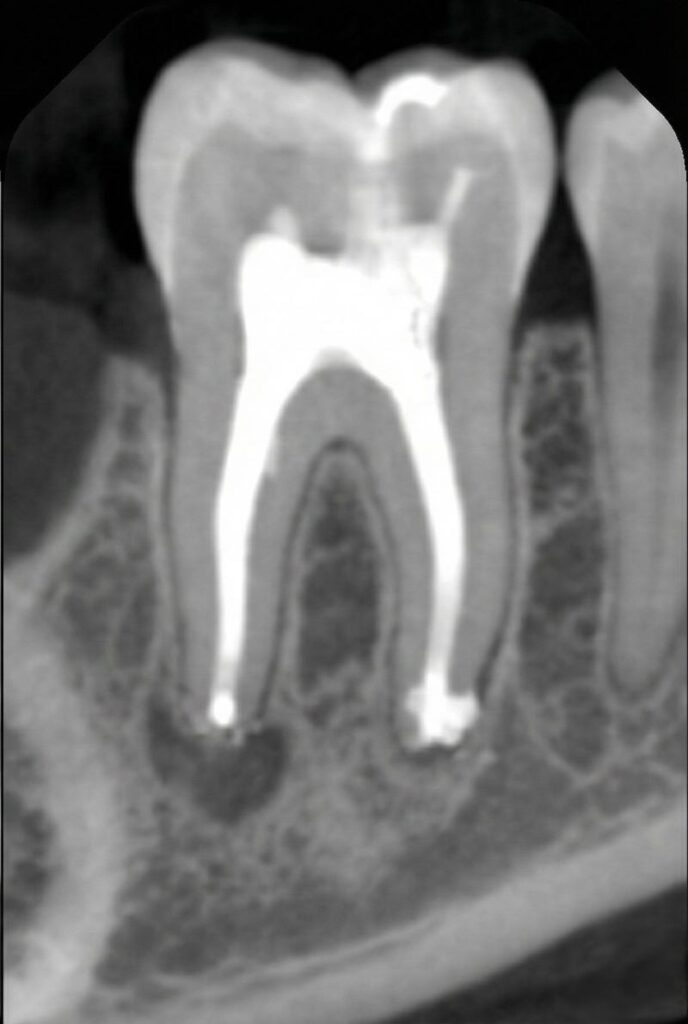

Root canal therapy is an endodontic procedure that removes diseased or inflamed pulp, disinfects the canals and seals them with gutta‑percha. After the canals are cleaned, the tooth is rebuilt with a filling or crown for strength and function. We offer retreatment root canals when previous therapy fails, a pulpotomy to partially remove the nerve in developing teeth and an apicoectomy (endodontic surgery) to remove infection at the root tip.

Digital 3‑D imaging, rotary instruments and ultrasonic irrigation help us clean canals thoroughly and perform efficient single‑visit treatments.